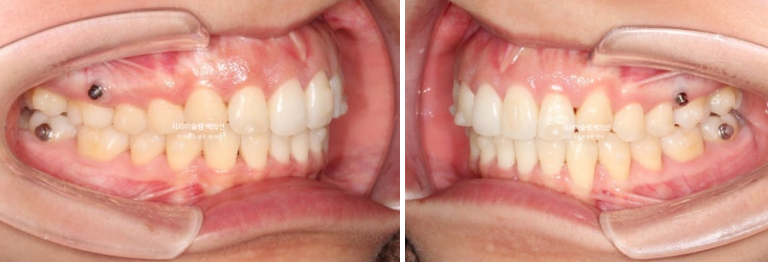

25.09

블랙트라이앵글 사이즈는 많이 줄였고 중심선은 잘 맞습니다.

어금니 교합은 물샐틈 없는 1급관계입니다.

이제 전 후 비교 보겠습니다.

총 치료기간은 2년입니다.

23.09~25.09

큰어금니가 약 2mm 사랑니 공간으로 잘 이동했습니다.